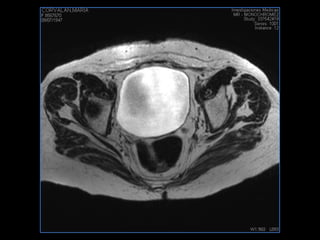

PROTOCOLO pelvis SAG T2, Y FAT SAT (FINOS) AXIAL T1  AX FAT SAT CON   GADOLINIO :  AX T1 Y COR T1 SAT: NO  FASE: RL THK: 3MM  COIL:  GAP: (FACTOR 1.4) 1MM FOV: 40 CM NEX:2 SINCRONIZACION RESPIRATORIA EN 3 O 4 CICLOS ALE

resonancia de abdomen